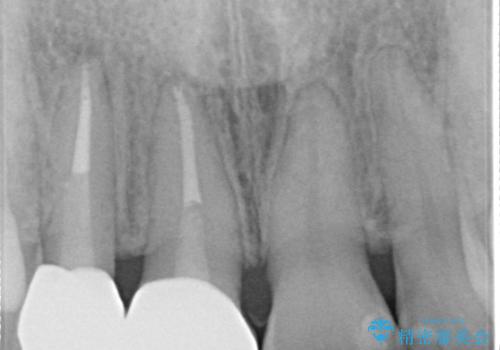

前歯が痛い。根管治療~オールセラミッククラウン

- 前歯が痛いことを主訴に来院されました。

根管治療を行った後、オールセラミッククラウン(エクセレント)にて治療を行いました。